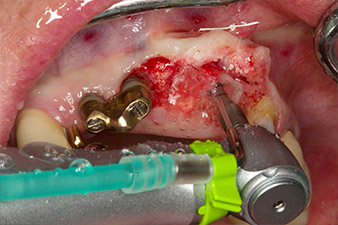

Xenogenic bone substitute material

Fig. 5: In order to achieve the best possible quality of peri-implant tissue, the site was additionally augmented with xenogenic bone replacement material and a collagen membrane in the scope of guided bone regeneration.